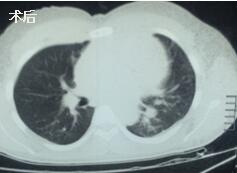

當(dāng)看到病人癥狀緩解�,復(fù)查胸部CT幾近完美�����,我們那種自豪感油然而生�����。偶爾去治愈,常常去幫助��,總是去安慰�,我們深知,小伙子的人生之路并不長����,只能深深祈禱他在我們的治療下能走得更遠(yuǎn)一些,能把剩下的日子走的更充實一些����。而我們在能夠幫助人的時候�,別一味地去安慰,永不言棄���,是我們這一群胸外人堅貞的信念。